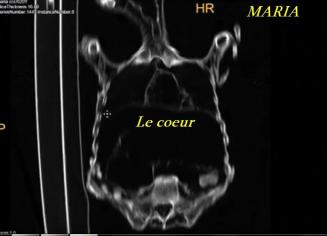

Planches (Dr José Rios de la Cruz) - Scanners (Dr Raymundo Salas Alfaro)

Scanners et radios de la grande "MARIA" de 168 cm

(cliquer sur les planches pour les agrandir)

Diaphragme et cœur

Cœur et bronches